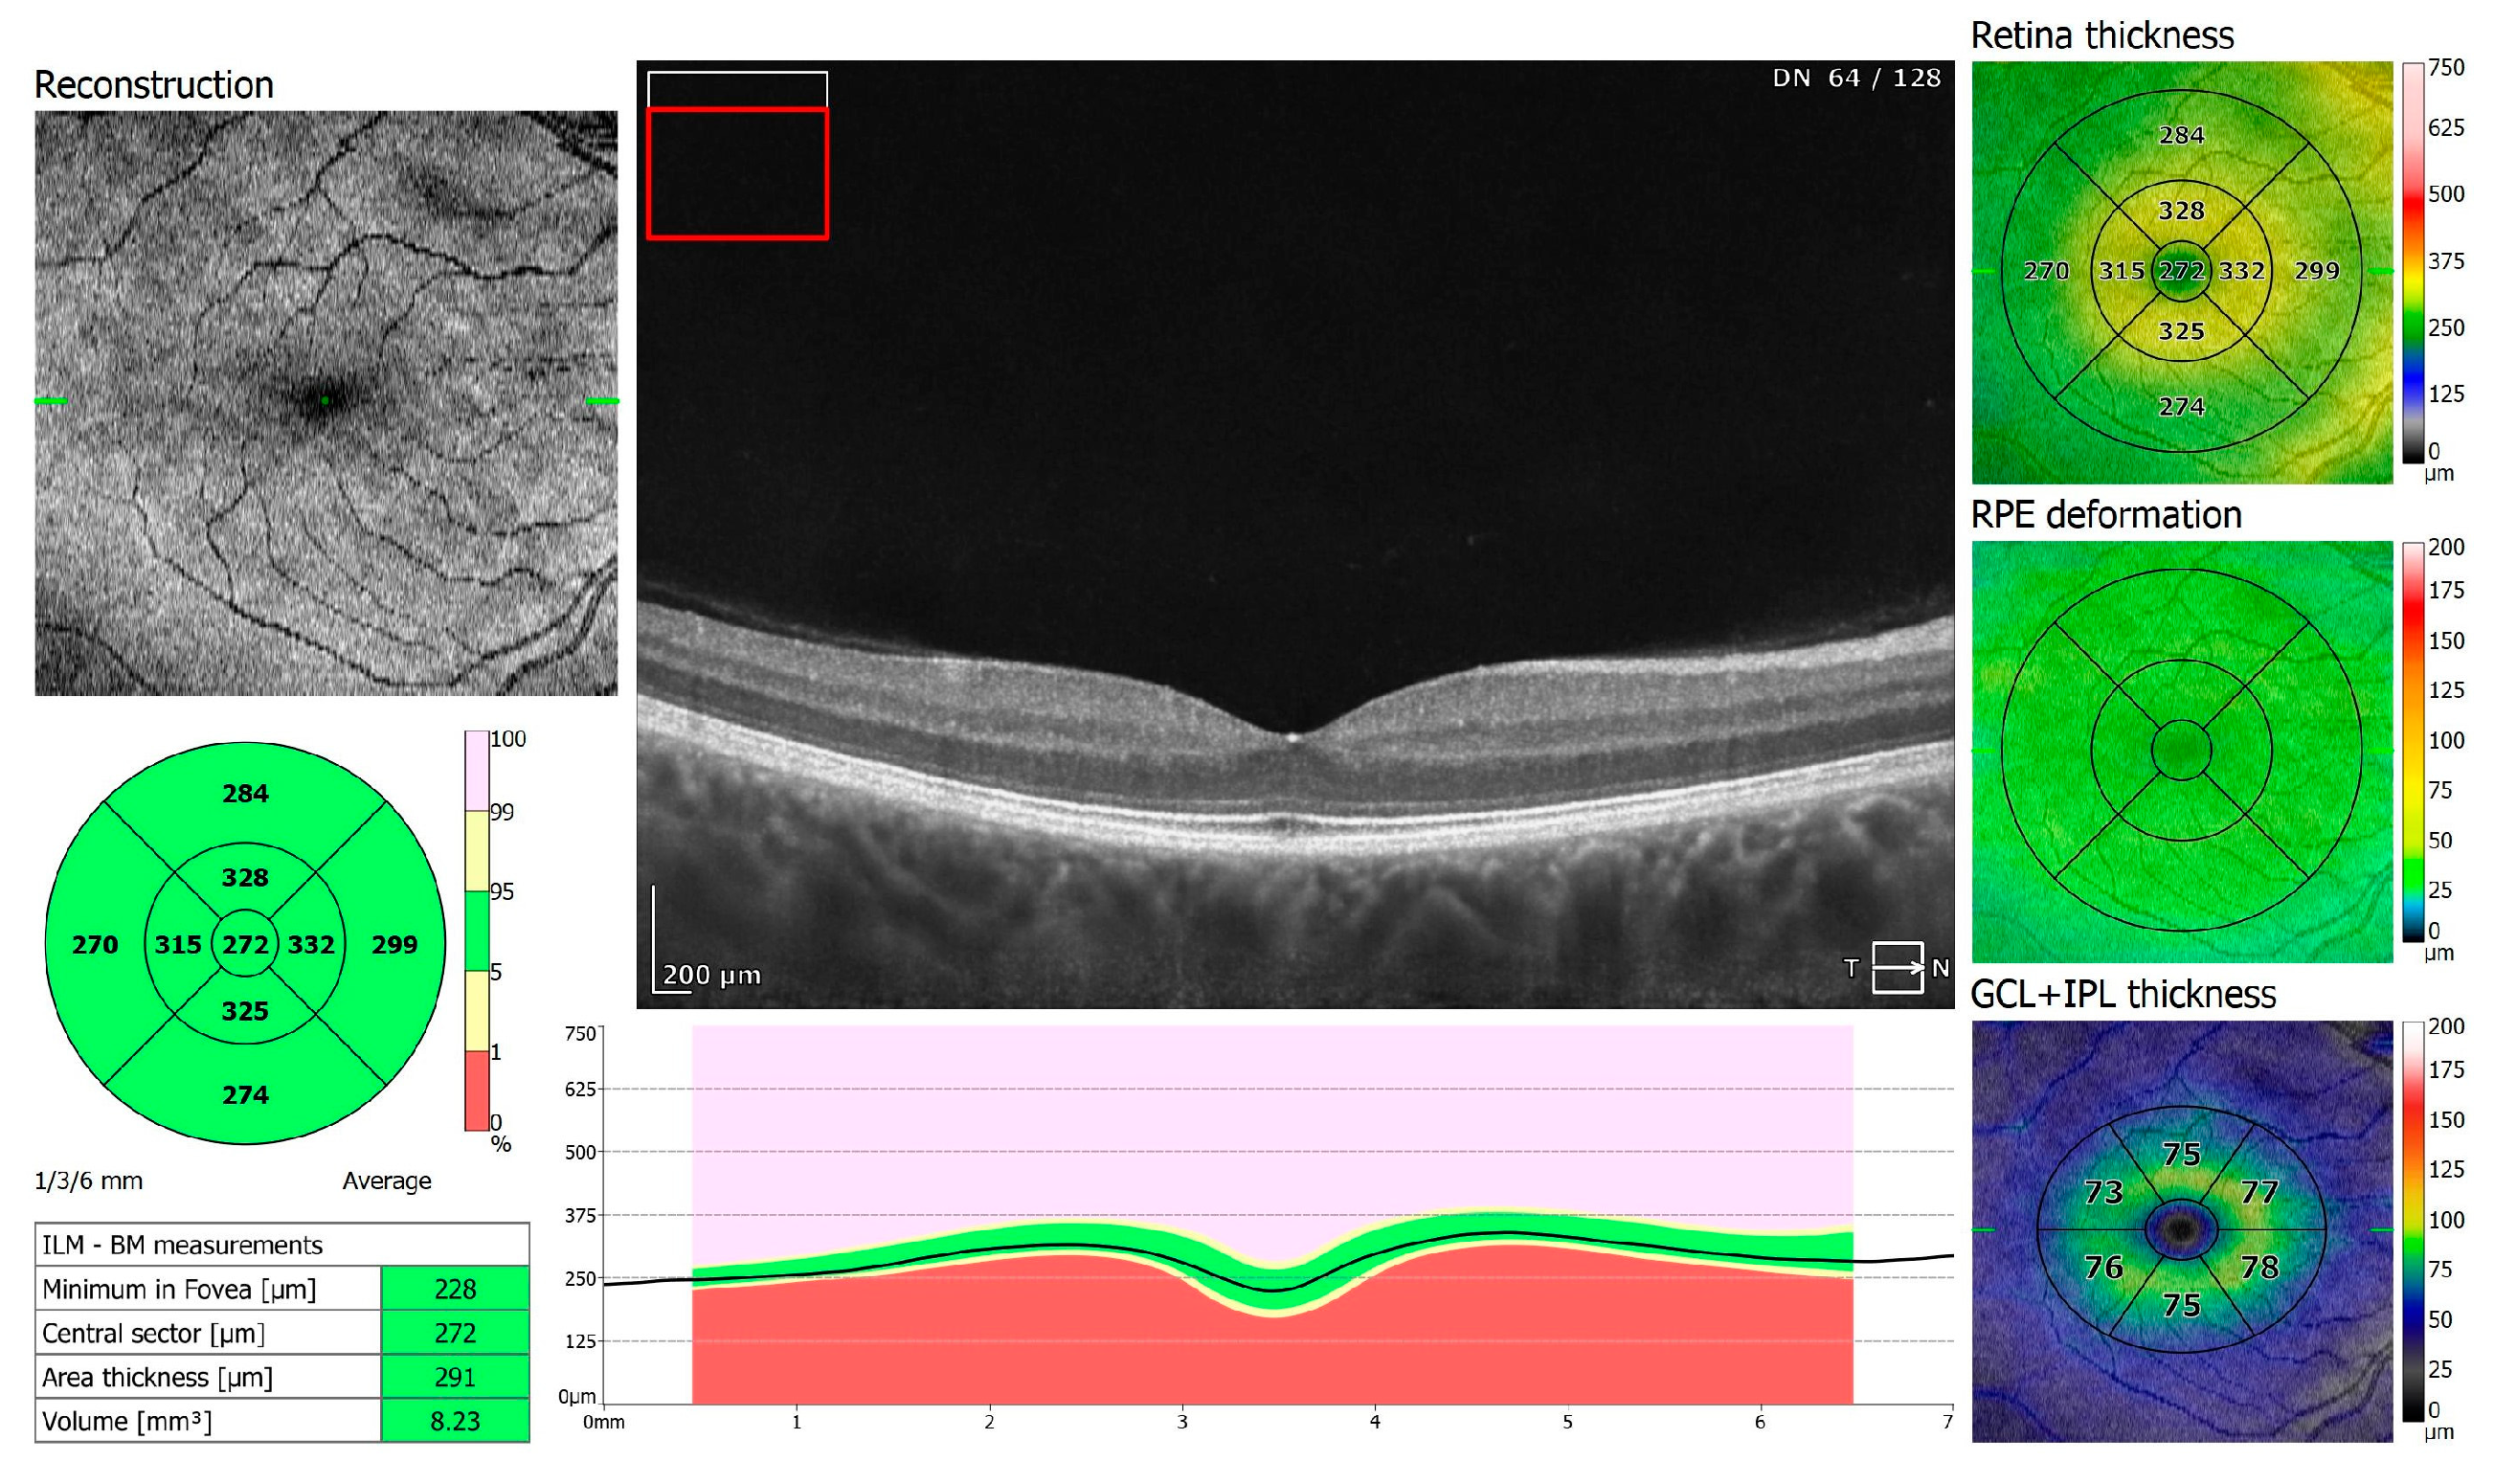

Figure 1.

OCT 3D macula scan 7 × 7 mm of COVID-19-positive patient. RPE, retinal pigment epithelium; GCL + IPL, ganglion cells layer + inner plexiform layer; ILM–BM, inner limiting membrane–Bruch’s membrane.

Of the participants, 20 received oxygen therapy at flow rates ranging from 1–10 L, while 4 received high-flow intranasal oxygen therapy (HFNOT). Additionally, 5 patients were treated with Remdesivir therapy, 5 received COVID-19 convalescent plasma therapy, and 11 were treated with Tocilizumab. The demographics and clinical characteristics of the study participants are presented in Table 1. The mean time from a positive PCR test to study enrollment was 13.23 days, with a standard deviation of 8.18 days. The control group comprised 38 healthy individuals: 28 men and 10 women (control versus research group: p = 0.21), with an average age of 58 years, ranging from 33 to 69 years. All participants underwent two examinations, one upon admission and another upon cessation of therapy (6.70 ± 6.46 days). Spectral-domain optical coherence tomography (SD-OCT) was conducted using REVO FC 130 (Optopol Technology, Zawiercie, Poland). This device allows for high-resolution imaging and quantitative analysis of both the retina and cornea. The study specifically evaluated central retinal thickness, retinal nerve fiber layer (RNFL) thickness and optic disc parameters, alongside central corneal thickness and corneal epithelium thickness. The measurements were performed using built-in retinal and corneal layer segmentation tools provided by the OCT system, which automatically segmented the different layers of the retina and cornea to ensure precise and repeatable thickness measurements. OCT protocols included a 3D macula 7 × 7 mm scan, 3D disc 6 × 6 mm scan, and anterior radial 8 × 8 mm scan (Figure 1, Figure 2, Figure 3, Figure 4, Figure 5 and Figure 6). All patients had also undergone slit lamp examination, including indirect ophthalmoscopy.